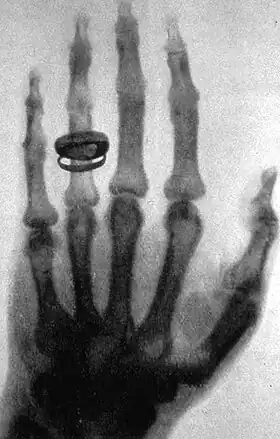

X-ray of a hand. X-rays are a common medical test. | |